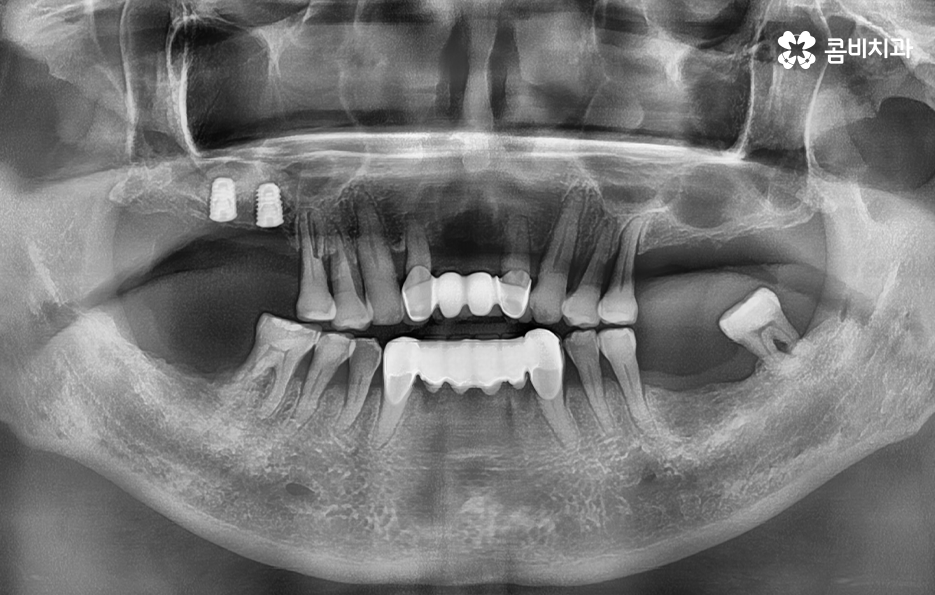

임플란트의 시술 원리는 잇몸 뼈에 식립하게 되기 때문에 충분한 골조직이 없을 때는 시술 성공률도 낮아질 뿐 아니라 장기적인 안정성도 떨어지기 때문에 잇몸 뼈가 부족하신 분들은 뼈이식을 추가적으로 해야할 수 있어요

만약 치주염으로 인해 50대임플란트 해야 하는 분들의 경우에는 뼈이식을 추가적으로 받아야 하는 경우가 있겠고 임플란트의 안정성을 확보하기 위해서는 임플란트를 고정해줄 수 있는 일정한 두께와 식립 깊이, 골질이 건강해야 하는데요

치주염이 심해지고 있다면 50대임플란트 치료를 보다 수월하게 받기 위해서도 치주염이 더 깊어지지 않도록 잇몸 치료도 미리 고려하는 것이 좋으며 주변 치아, 잇몸의 악화로 이어지지 않도록 주의하실 필요가 있어요

또한 뼈이식을 해야 하더라도 잇몸을 되도록 보존하는 치료를 하고 치료 시점을 의사와 잘 상의한다면 뼈이식의 양을 줄일 수 있고 회복기간도 상대적으로 줄일 수 있다는 점에서 임플란트 치료 원리를 먼저 이해하시고 대처하시길 바라고 있어요